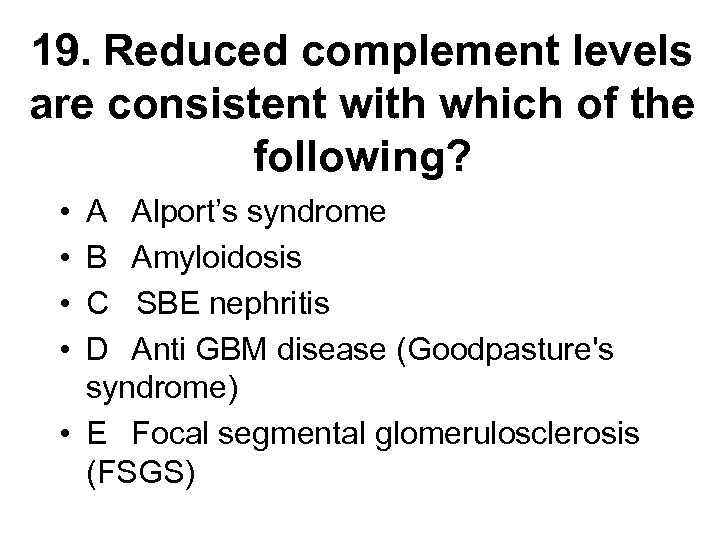

18 With regard to lupus nephritis: • A It may present with a rapidly progressive glomerulonephritis • B It may present with histological changes similar to diabetic nephropathy • C It should be treated with oral steroids alone when associated with a membranous histology • D It should only be treated with cytotoxic agents when serum creatinine > 120 mol/l • E Frequently complicates drug induced SLE

18 With regard to lupus nephritis: • A It may present with a rapidly progressive glomerulonephritis • B It may present with histological changes similar to diabetic nephropathy • C It should be treated with oral steroids alone when associated with a membranous histology • D It should only be treated with cytotoxic agents when serum creatinine > 120 mol/l • E Frequently complicates drug induced SLE

Lupus nephritis • Aetiology • - renal involvement occurs to some degree in most lupus patients, though drug induced lupus is said to spare the kidney • Presentation • - can vary from asymptomatic urine abnormalities to HT, NS, ARF, CRF • Diagnosis • - all patients with lupus and urine abnormalities should have biopsy to guide potentially toxic treatment regardless of serum creatinine. Histology can change from one type to another in the same patient. Six distinct patterns are recognised. Histology not similar to that of DN • 1 - normal • 2 a - mesangial deposits 2 b - mesangial hypercellularity • 3 - focal and segmental proliferative GN • 4 - diffuse proliferative (>50% glomeruli involved) causing RPGN • 5 - membranous • 6 - glomerulosclerosis

Lupus nephritis • Aetiology • - renal involvement occurs to some degree in most lupus patients, though drug induced lupus is said to spare the kidney • Presentation • - can vary from asymptomatic urine abnormalities to HT, NS, ARF, CRF • Diagnosis • - all patients with lupus and urine abnormalities should have biopsy to guide potentially toxic treatment regardless of serum creatinine. Histology can change from one type to another in the same patient. Six distinct patterns are recognised. Histology not similar to that of DN • 1 - normal • 2 a - mesangial deposits 2 b - mesangial hypercellularity • 3 - focal and segmental proliferative GN • 4 - diffuse proliferative (>50% glomeruli involved) causing RPGN • 5 - membranous • 6 - glomerulosclerosis